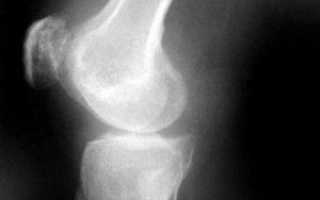

От общего числа всех заболеваний, связанных с палочкой Коха, на туберкулез костей и суставов приходится 3,4%. Тем не менее именно кости являются наиболее распространенным местом данной инфекции, после легких. Чаще всего туберкулез костей поражает позвоночник. Так происходит в 40% случаев. Далее по 20% отводится на коленный и тазобедренный суставы. А вот диагностировать туберкулез других частей тела, врачам доводится достаточно редко.